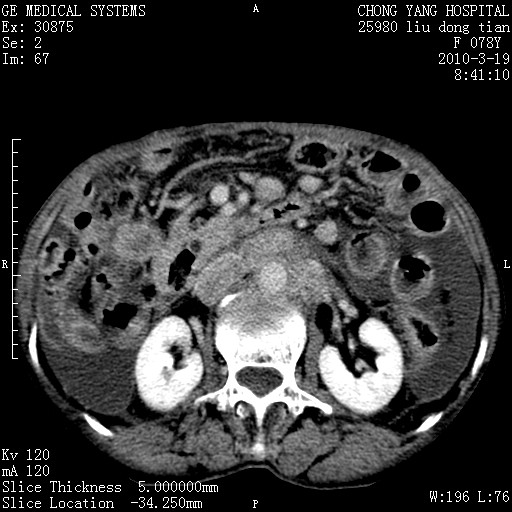

标题: CT25199:F 78Y 腹胀半年 消瘦乏力 [打印本页]

胆囊壁增厚并明显强化,胆囊癌伴多发转移瘤可能性大,淋巴瘤不除外,右肾囊肿,胸腹水.

考虑nhl,肝、脾、腹膜腔及腹膜后多发淋巴结受侵,腹水,右肾囊肿,慢性胆囊炎,右侧少量胸腔积液。

首先考虑恶性淋巴瘤 。

胰头有肿块形成,胰头ca伴肝脾、腹膜腹膜后转移

胆囊有软组织影有强化,支持胆囊癌,肝脾、腹膜后淋巴结转移。

nhl的淋巴结多围绕主动脉,而且主动脉会移位,所以不考虑nhl。

分开来讲:肝左叶、尾叶病灶有不均强化像肝癌;

脾脏病灶无强化,像多发囊肿或淋巴管瘤,不除外淋巴瘤(低强化);

胆囊增生性病变:胆囊癌,腺肌增生症,慢性胆囊炎;

肝门、胰腺头、腹膜后多个团块: 淋巴瘤,转移;

腔静脉肝内段细小有无布加可能?

一元论最好了 淋巴瘤所致改变; 胆囊癌转移不像,胆囊周围肝组织清晰,肝癌淋巴结转移?三元论都不止。

胰头ca伴肝脾、腹膜腹膜后转移!

最后报的胰头癌多发转移,脾脏单独考虑囊肿或淋巴管瘤。